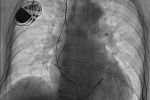

起搏人生——心内科独立完成3例心脏永久起搏器植入术

8月的一天,心内科温馨的病房内,一位悠然的老人正与他的家人谈笑风生。陪老人聊天的女儿说这几天父亲吃得香,睡的甜,今天就要出院了,别提有多高兴了。若无人介绍,谁也看不出眼前这位老人一周前正被病痛折磨着挣扎在生死边缘。老人今年81岁,经常无故出...